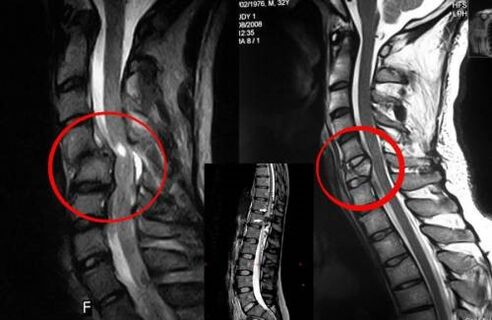

Diagnosi

L'osteocondrosi vertebrale richiede una consultazione tempestiva con un medico che aiuterà a ripristinare la schiena danneggiata. I dispositivi moderni consentono la diagnosi nelle prime fasi dello sviluppo. In caso di patologia contattare un neurologo o un ortopedico. Innanzitutto, viene effettuato un esame della colonna vertebrale ferita e viene presa un'anamnesi, quindi vengono prescritti metodi diagnostici di laboratorio e strumentali che rilevano l'osteocondrosi:

- raggi X;

- mielografia;

- esame neurologico;

- TC e RM;

- Risonanza magnetica nucleare.